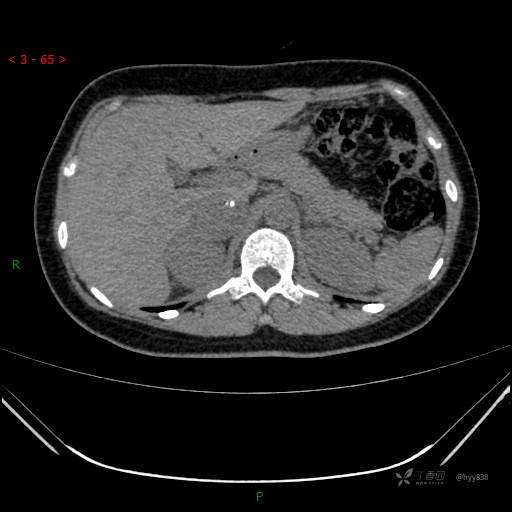

辅助检查:CT

讨论:病变性质?